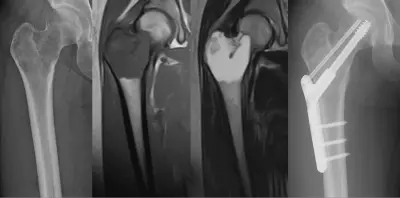

[20代 右大腿骨近位部腫瘍] 良性骨腫瘍に対して腫瘍掻把+内固定術施行。